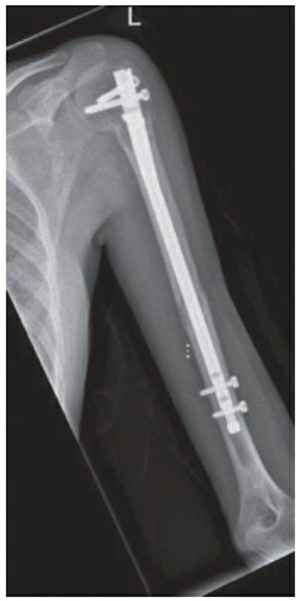

🔍 Click to enlargeFigure 4: Plate and screw fixation of a distal third humeral shaft fracture. - **Intramedullary Nailing (IMN):**

- **Relative Indications:** Pathologic fractures, segmental fractures, severe osteoporotic bone, overlying skin compromise limiting open approach, and polytrauma.

🔍 Click to enlargeFigure 5: Intramedullary nail fixation of a humeral shaft fracture. - **External Fixation:**